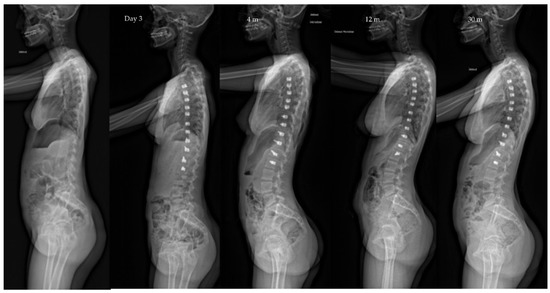

| Pre-op | Post-op Day 3 | Post-op 1y | Last f/u | p-Value | |

| Major curve | 49°(8,9°) | 27°(12°) | 22°(12°) | 19°(14°) | <0.01 |

| Secondary curve | 27°(14°) | 23°(15°) | 22°(11°) | 17°(10°) | <0.01 |

| Instrumented curve | NA | 26°(11°) | 23°(10°) | 20°(14°) | <0.01 |

| Kyphosis (T1–T12) | 20°(13°) | 23°(13°) | 25°(12°) | 24°(14°) | 0.06 |

| Lordosis (L1–L5) | 36°(12°) | 32°(13°) | 40°(7°) | 40°(8°) | 0.07 |